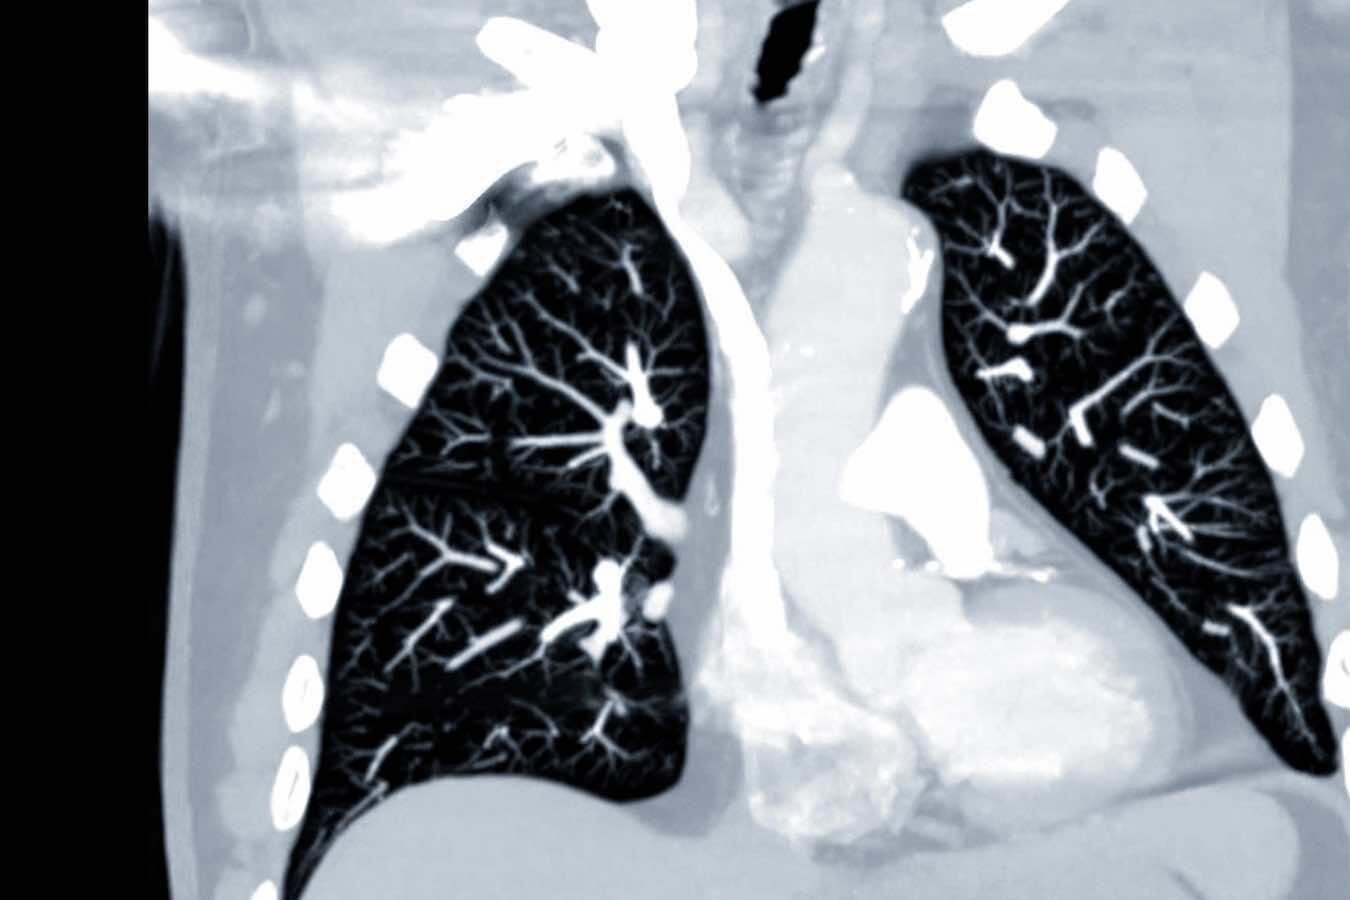

Die Kardiologie ist die Lehre vom Herzen und seinen Erkrankungen. Bei KardioPro bieten wir eine umfassende Bandbreite an diagnostischen Verfahren, um die Funktion und Struktur Ihres Herzens präzise zu beurteilen. Dazu gehören unter anderem das Ruhe- und Belastungs-EKG, der Langzeit-EKG zur Detektion von Herzrhythmusstörungen, sowie der Herzultraschall (Echokardiographie) zur Beurteilung der Herzklappen und der Pumpleistung.

Umfassende kardiologische Vorsorgeuntersuchungen basierend auf den Zusatzqualifikationen Hypertensiologie (DHL) und Lipidologie (DGFF). Wir nutzen modernste Ultraschall- und EKG-Techniken zur frühzeitigen Erkennung komplexer kardiovaskulärer Risikofaktoren und Gefäßveränderungen.

Die drei Säulen unserer Praxis – Präventions-Diagnostik, Spezialsprechstunden und Kardiovaskuläre Leistungsanalyse – sind eng miteinander verzahnt, um dieses Ziel zu erreichen. Durch die detaillierte Diagnostik, die bis zur Kardiovaskulären Schlafmedizin reicht, erkennen wir komplexe Zusammenhänge, die andernorts oft übersehen werden. Beispielsweise legen wir einen besonderen Fokus auf das Herz-Hirn-Gefäß-System: Risikofaktoren wie unbehandelter Bluthochdruck oder Herzrhythmusstörungen sind nicht nur für das Herz, sondern auch für die Gehirngesundheit und das Schlaganfallrisiko entscheidend. Mittels spezieller Gefäßuntersuchungen tragen wir aktiv dazu bei, diese Risiken frühzeitig zu entschärfen.